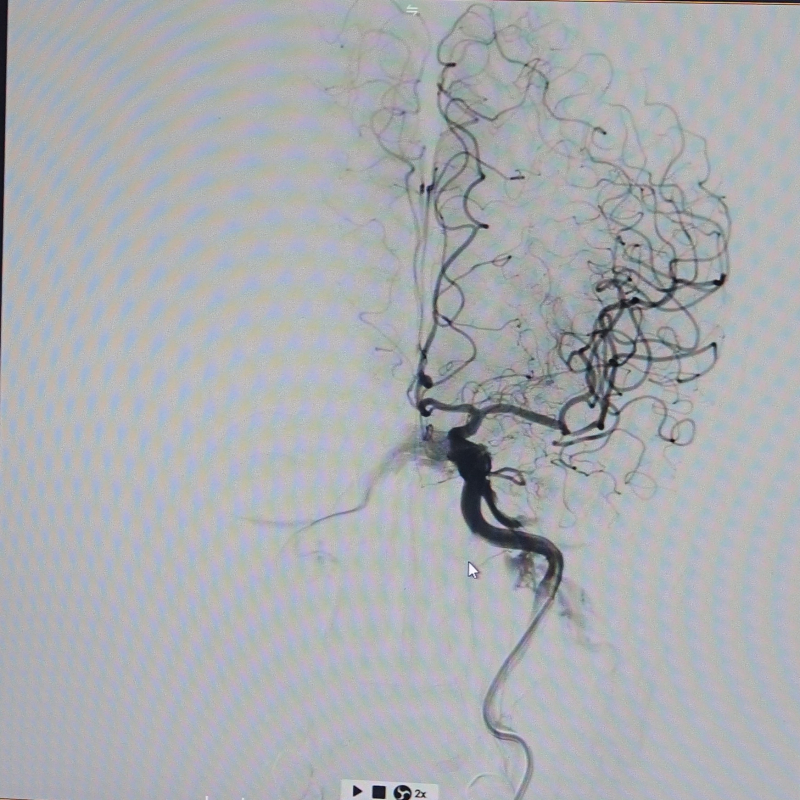

Để đánh giá chính xác tổn thương, bệnh nhân được chỉ định chụp mạch máu não bằng phương pháp chụp mạch số hóa xóa nền (DSA). Kết quả cho thấy gốc động mạch cảnh trong bên phải bị hẹp rất nặng, khoảng 90%. Đây là một trong số nguyên nhân chính gây giảm tưới máu bán cầu não phải, dẫn đến tình trạng yếu liệt nửa người trái của bệnh nhân.

Hình ảnh: Trước can thiệp